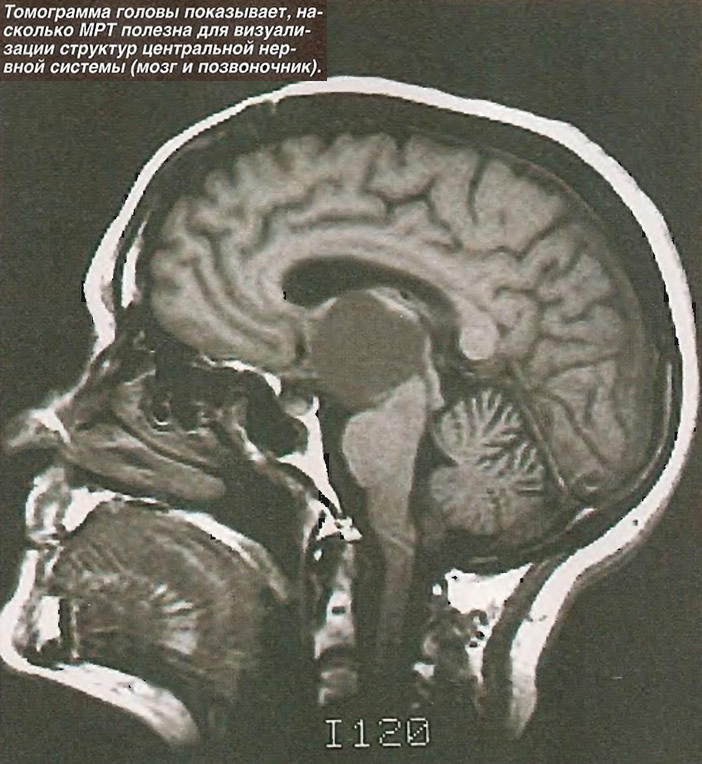

Демиелинизирующие заболевания мозга: МРТ изображения

Раздел: Путеводитель по жизни